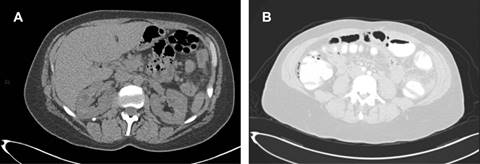

Mujer de 55 años, quien acudió por dolor de siete días de evolución en el flanco y la fosa iliaca izquierda, el cual aumentó en forma gradual. Negó fiebre, náusea, vómito o alguna otra sintomatología. Su médico le solicitó colonografía por tomografía axial computarizada (TAC), en la cual se advirtió la presencia de múltiples imágenes de aspecto quístico en la pared del yeyuno, del colon transverso, del ángulo esplénico y descendente, así como la presencia de pequeñas burbujas de aire en el espacio subdiafragmático derecho y la cavidad abdominal con respecto al neumoperitoneo (Figura 1).

Figura 1: Tomografía computarizada simple de abdomen, en la cual se pueden observar imágenes quísticas en el colon transverso y un ángulo esplénico (A), y corte axial con ventana para pulmón, que muestra aire libre en la cavidad abdominal (B).